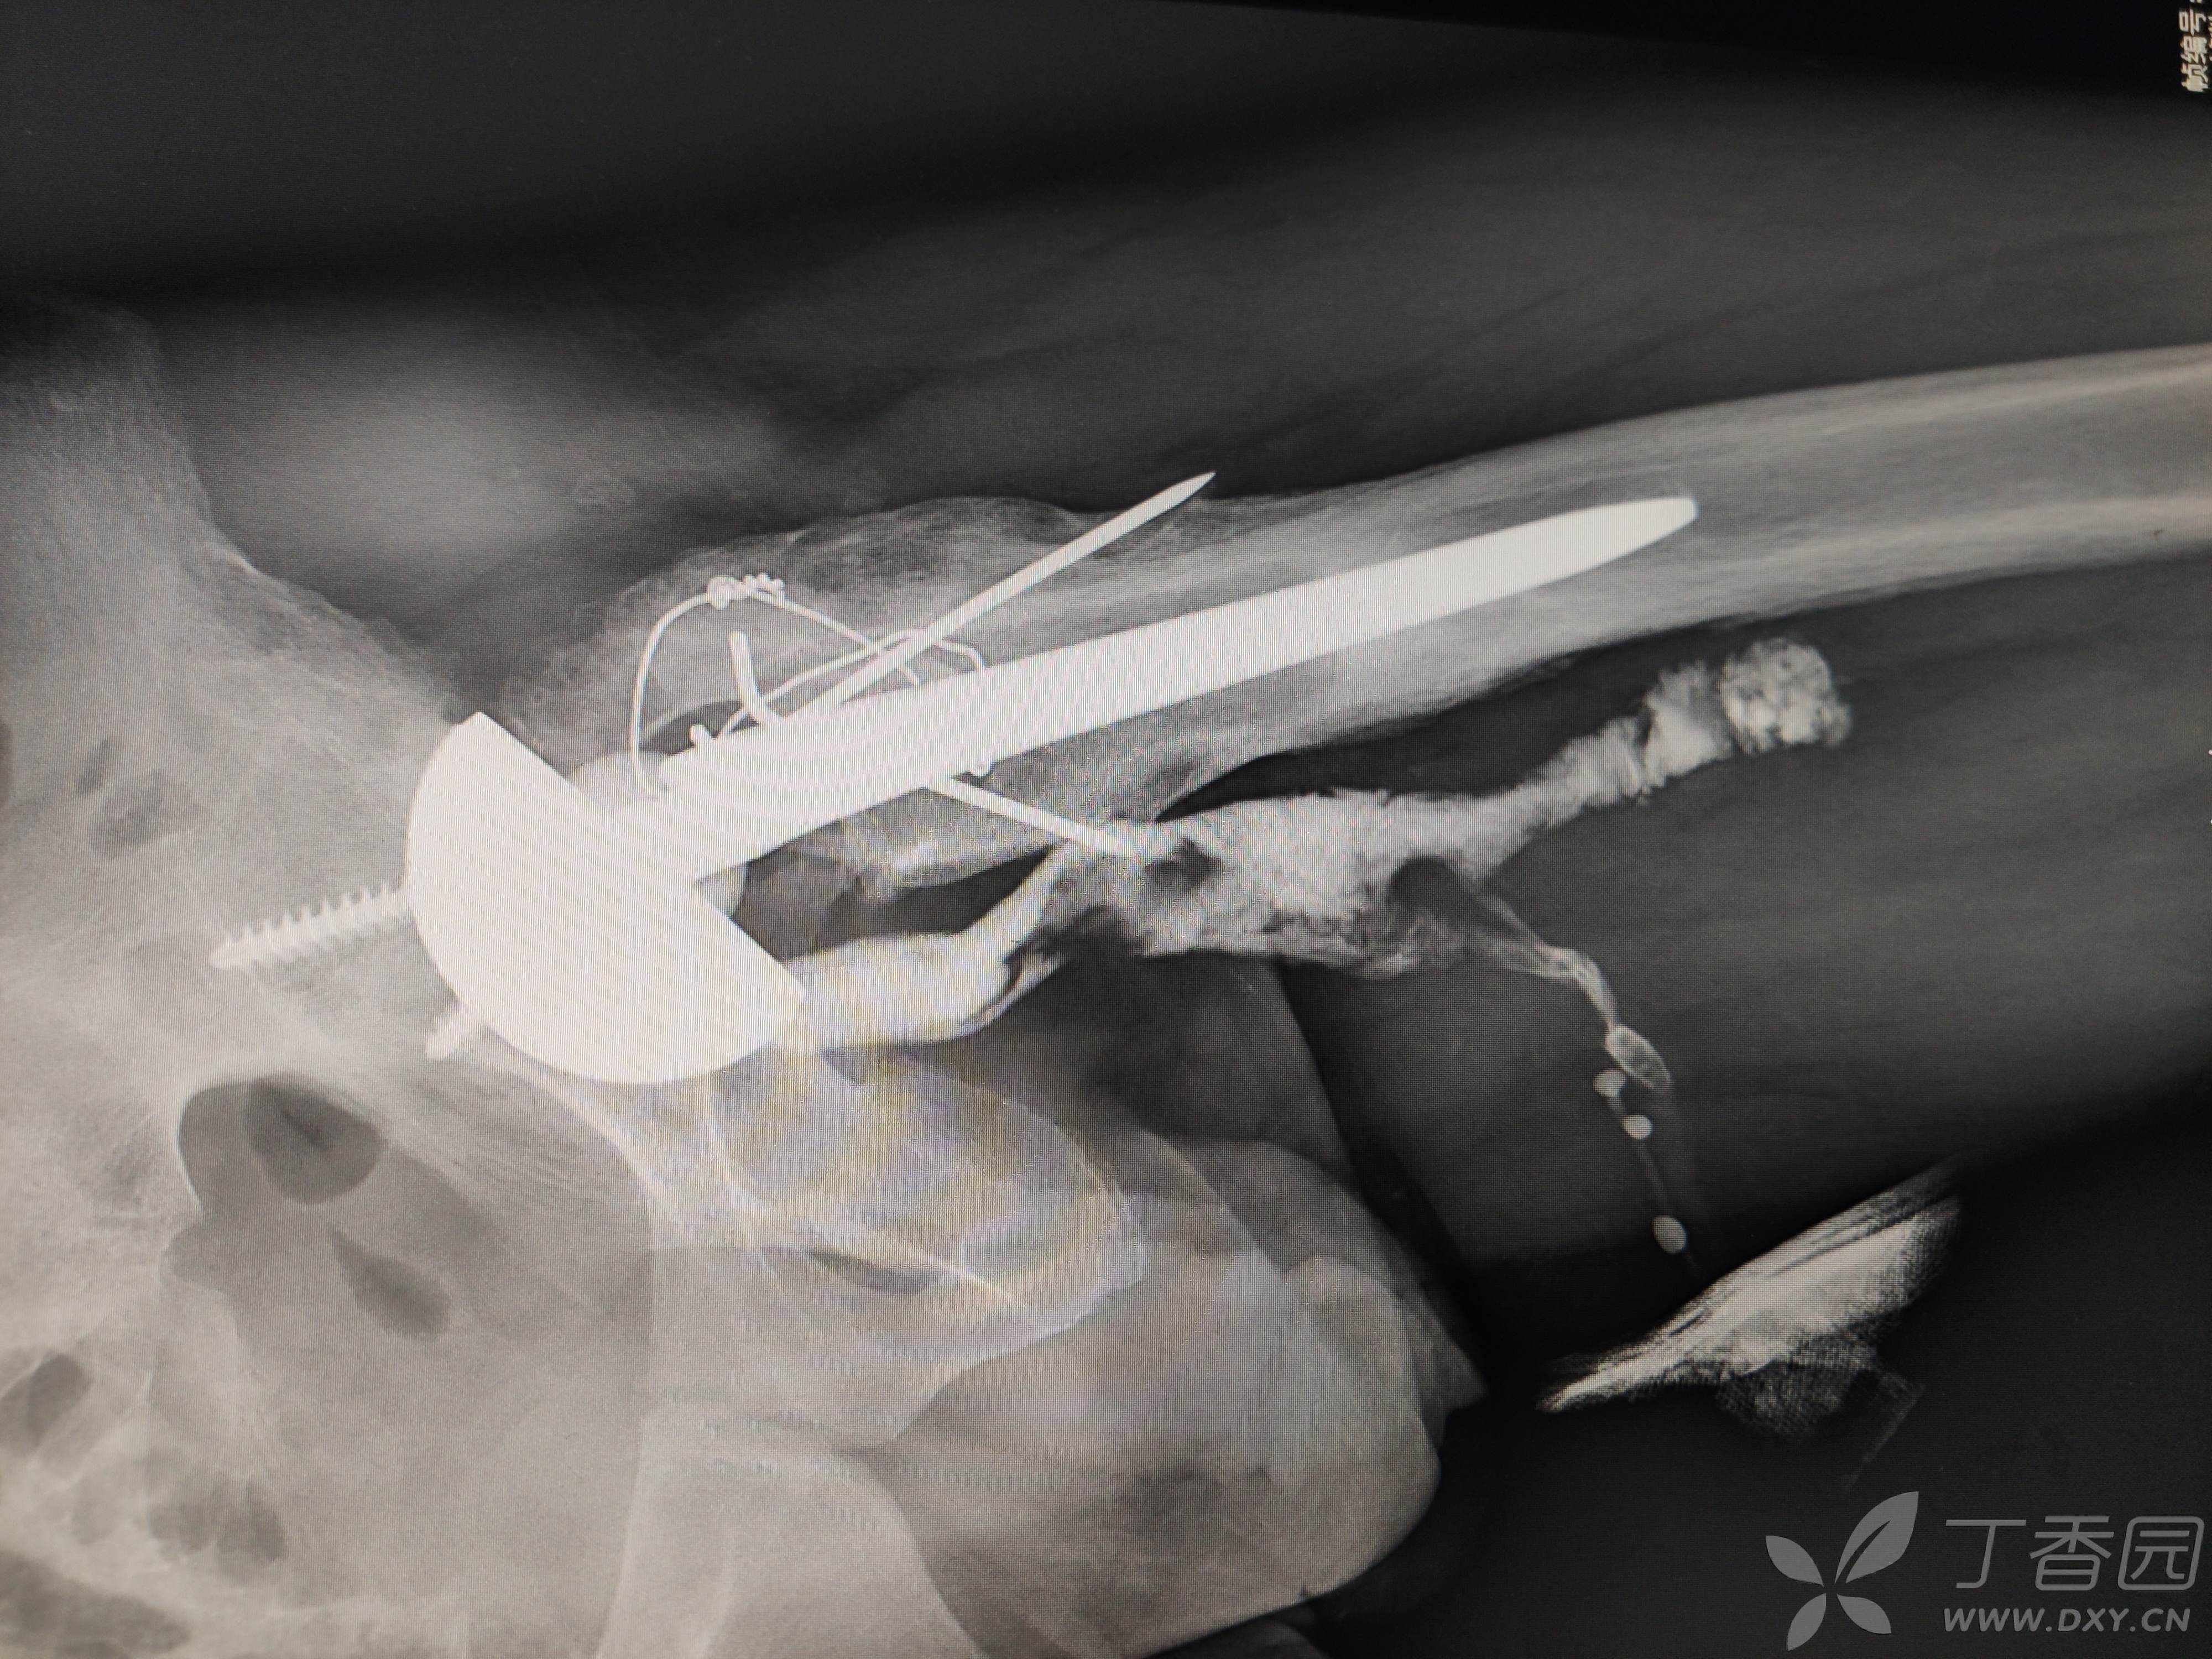

髋关节置换术后12年,大腿前内侧窦道1年,再发2周

患者12年因车祸伤致左股骨头粉碎性骨折,行左侧髋关节置换术,术后伤口愈合良好,左下肢轻度跛行,行走尚可,无疼痛。

辅助检查:近期的ESR(血沉) 32mm/h↑,hsCRP(高敏C反应蛋白) 25.55mg/L↑,PCT(降钙素原)0.03ng/ml,正常。血常规正常。X线片及CT是近期的。12年前的影像资料缺失。

抱歉,上传上来是横躺着的